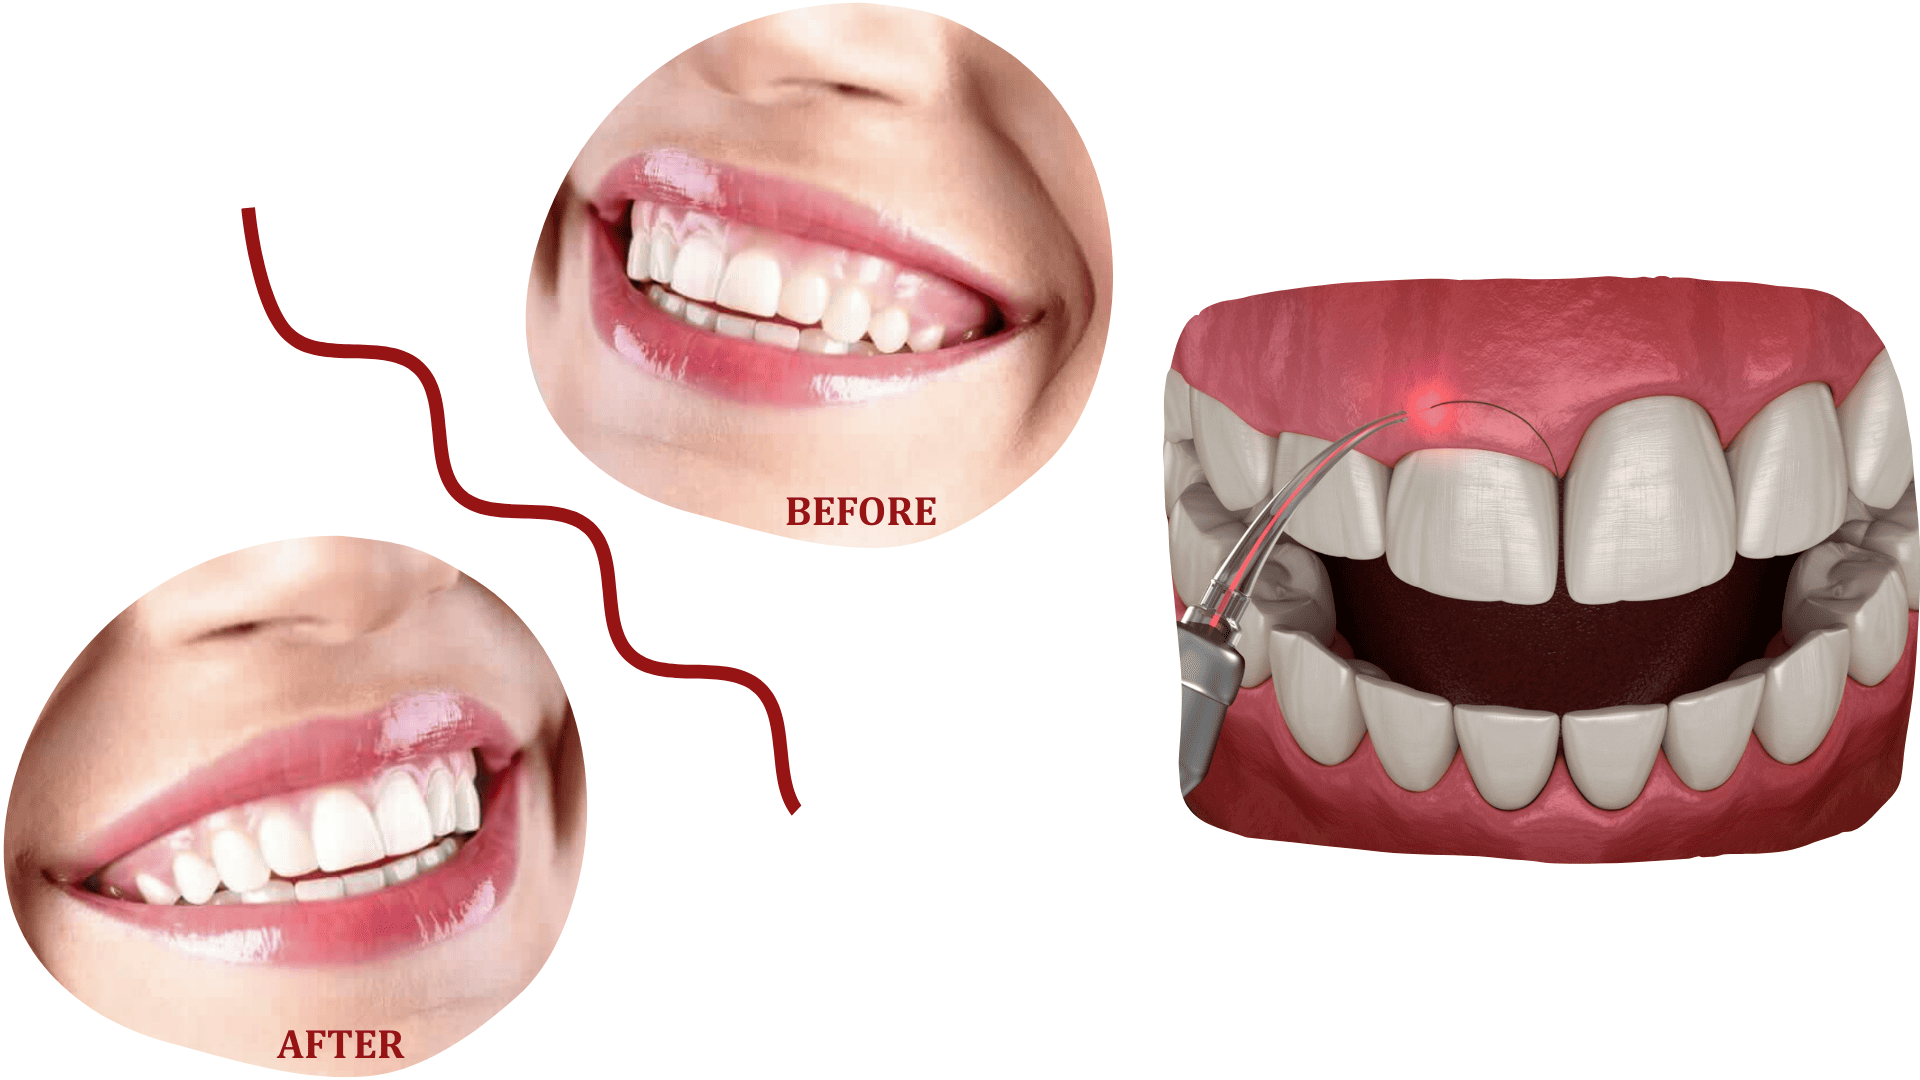

GINGIVECTOMY

Gingivectomy is a procedure in which excess gum tissue (gingiva) is removed, either for health or aesthetic reasons.

It is performed in patients with periodontal diseases and gum inflammation, as well as in those who require removal of excess gum tissue for aesthetic smile correction.

The procedure is performed under local anaesthesia, and recovery is rapid and painless.